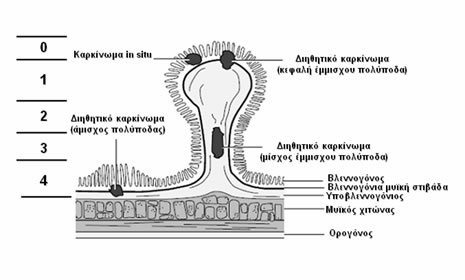

Η ταξινόμηση κατά Haggitt (Εικόνα 4) βασίζεται στο επίπεδο διήθησης:

- Επίπεδο 0: Χωρίς διήθηση, βαρειά δυσπλασία

- Επίπεδο 1: Το καρκίνωμα διηθεί διά της υποβλεννογονίου μυϊκής στιβάδας, αλλά περιορίζεται στην κεφαλή του έμμισχου πολύποδα

- Επίπεδο 2: Το καρκίνωμα διηθεί έως τον αυχένα, το όριο μεταξύ της κεφαλής και του μίσχου του έμμισχου πολύποδα

- Επίπεδο 3: Το καρκίνωμα διηθεί το μίσχο του έμμισχου πολύποδα

- Επίπεδο 4: Το καρκίνωμα διηθεί τον υποβλεννογόνιο χιτώνα του εντέρου κάτω από το μίσχο του έμμισχου πολύποδα. Όλοι οι κακοήθεις άμισχοι αδενωματώδεις πολύποδες είναι επιπέδου 4 κατά Haggitt.

Ο κίνδυνος λεμφαδενικών μεταστάσεων είναι <1% για έμμισχους κακοήθεις πολύποδες με επίπεδο διήθησης κατά Haggitt 1, 2 και 3, ενώ για τα αδενώματα με επίπεδο 4 κατά Haggitt, έμμισχα ή άμισχα, ο κίνδυνος αυτός κυμαίνεται σε 12 έως 25%.

Η ενδοσκοπική πολυπεκτομή αρκεί για τα καοήθη αδενώματα με επίπεδο διήθησης κατά Haggitt 1, 2 και 3, εφόσον το κακόηθες νεόπλασμα δεν είναι κακής διαφοροποίησης και δεν ανευρίσκεται διήθηση των λεμφαγγείων ή των αγγείων του υποβλεννογόνιου χιτώνα.

Εικόνα 4.

Ταξινόμηση κατά Haggitt